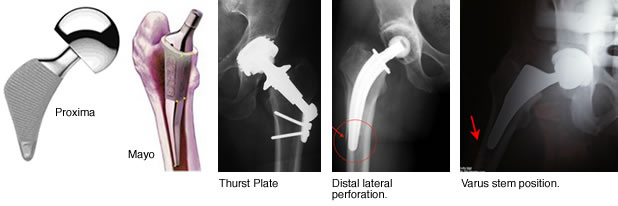

A number of bone conserving hip joints have been developed and have been used instead of conventional femoral stems. First generation stems include Munting, Weber- Huggler Thrust Plate, Stratech, Spiron, Spotorno and the Mayo.

Second generation stems such as the Silent, Proxima, McMinn, Proximal Epiphyseal Replacement (PER), CFP (Pipino) are now in use.

The risk of some short stems is perforation of the cortical bone, stress shielding and bone loss with a faith driven belief in some that metaphyseal fit and fill alone will suffice for stability ignoring the hoop and mechanical strength of the proximal neck and superior (intact) digital fossa bone flowing in to the greater trochanter.